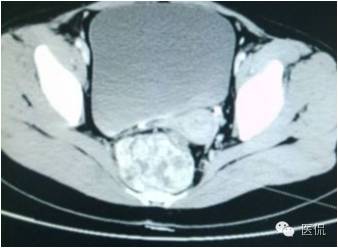

病史

女,37岁,体检超声发现盆腔包块一周。无其他异常。

CT平扫(CT值23HU)

增强动脉期(CT值31HU)

增强静脉期(CT值62HU)

增强延迟期(CT值106HU)

结果

手术是:盆腔占位,病理为:血管肌纤维母细胞瘤。与肛门粘连,于是同时做了肛门的处理。